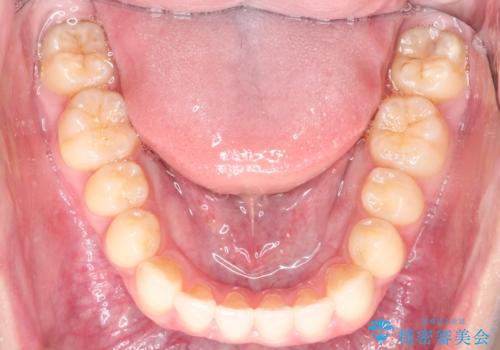

前歯のデコボコ インビザラインによる目立たない矯正

- 前歯のデコボコを主訴に来院された患者様です。

目立たないそうちをご希望されたので、インビザラインにて治療することとしました。

歯と歯の間をわずかに削ってスペースをつくり、デコボコを改善しました。